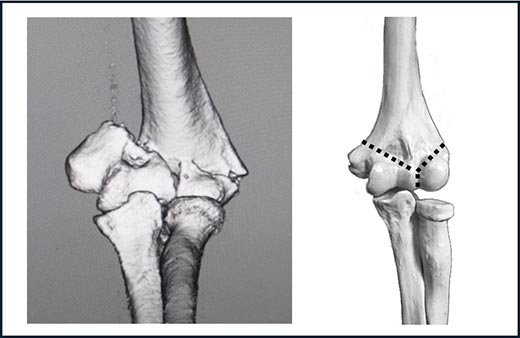

- 上腕骨顆部関節内骨折(〜かぶかんせつないこっせつ)

上腕骨内側顆、上腕骨外側顆、上腕骨滑車や上腕骨小頭を含む骨折です(図3)。若年者や中高年者に多く、高エネルギー外傷のような大きな力で発生します。関節面で骨折しているため整復(良い位置に戻すこと)が難しく、ギプスで固定して骨をつけようとすると、関節面が転位(ズレ)したままになります。

図3.上腕骨顆部関節内骨折:上腕骨内顆、上腕骨外顆、

上腕骨滑車と上腕骨小頭を含む骨折で、関節面に転位があります。